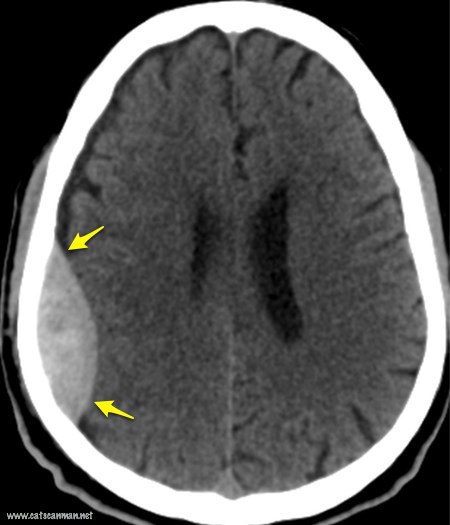

Кроме того, для того чтобы определить какая именно гематома у человека назначают компьютерную томографию (КТ) или магнитно-резонансную томографию (МРТ), так как по общеклиническим симптомам поставить верный диагноз нельзя.

При проведении КТ и МРТ исследований врачу будет ясна полная картина происходящего. Чаще, эпидуральные гематомы на снимке, полученной при КТ образуют двояковыгнутую линзу, притом как субдуральные – серп. Причем неважно какой вид – подострая субдуральная гематома или острая, в любом случае будет серп.